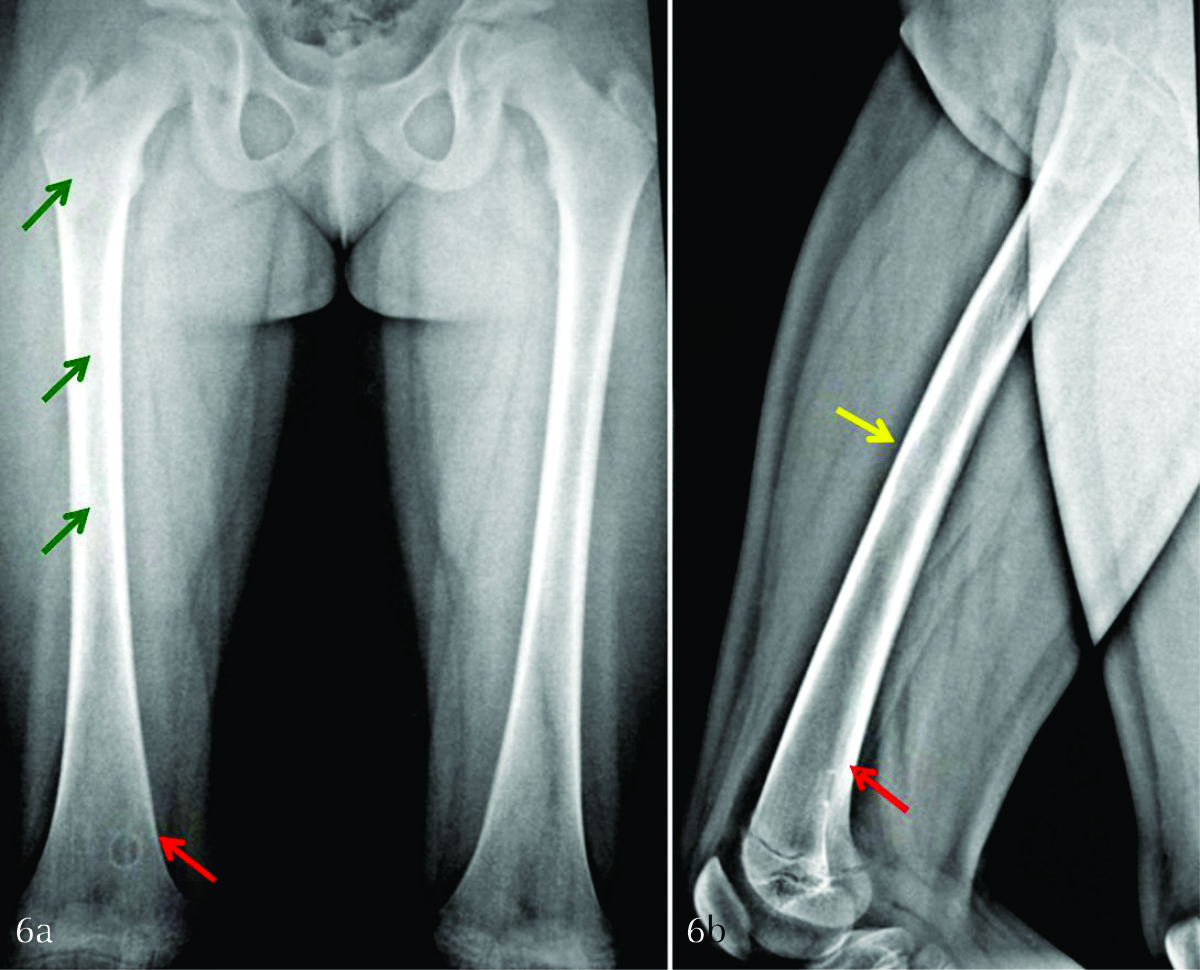

FAT SAT y T1 FAT SAT tras la administración de gadolinio en los tres planos del espacio (Ver fig. 4). Con el fin de determinar la distribución de las lesiones y valorar posibles lesiones en sitios insospechados se solicitó SPECT con 99Tc-MDP (Ver fig. 5). Dada la intensa captación del fémur homolateral se completó con radiografía simple de muslo derecho en proyección de frente y de perfil, identificándose lesiones radiolúcidas incipientes en la medular de la diáfisis femoral, con festoneado endóstico (Ver fig. 6).

Figura 6

a) Radiografía bilateral en proyección anteroposterior de fémur. b) Radiografía de fémur derecho de perfil. Se identifican lesiones radiolúcidas incipientes, en diáfisis de fémur derecho (flechas verdes), con festoneado endóstico (flecha amarilla). A su vez, se aprecia una lesión cortical, lítica, geográfica, bien delimitada, con anillo esclerótico (1b), en probable relación a fibroma no osificante (flechas rojas).